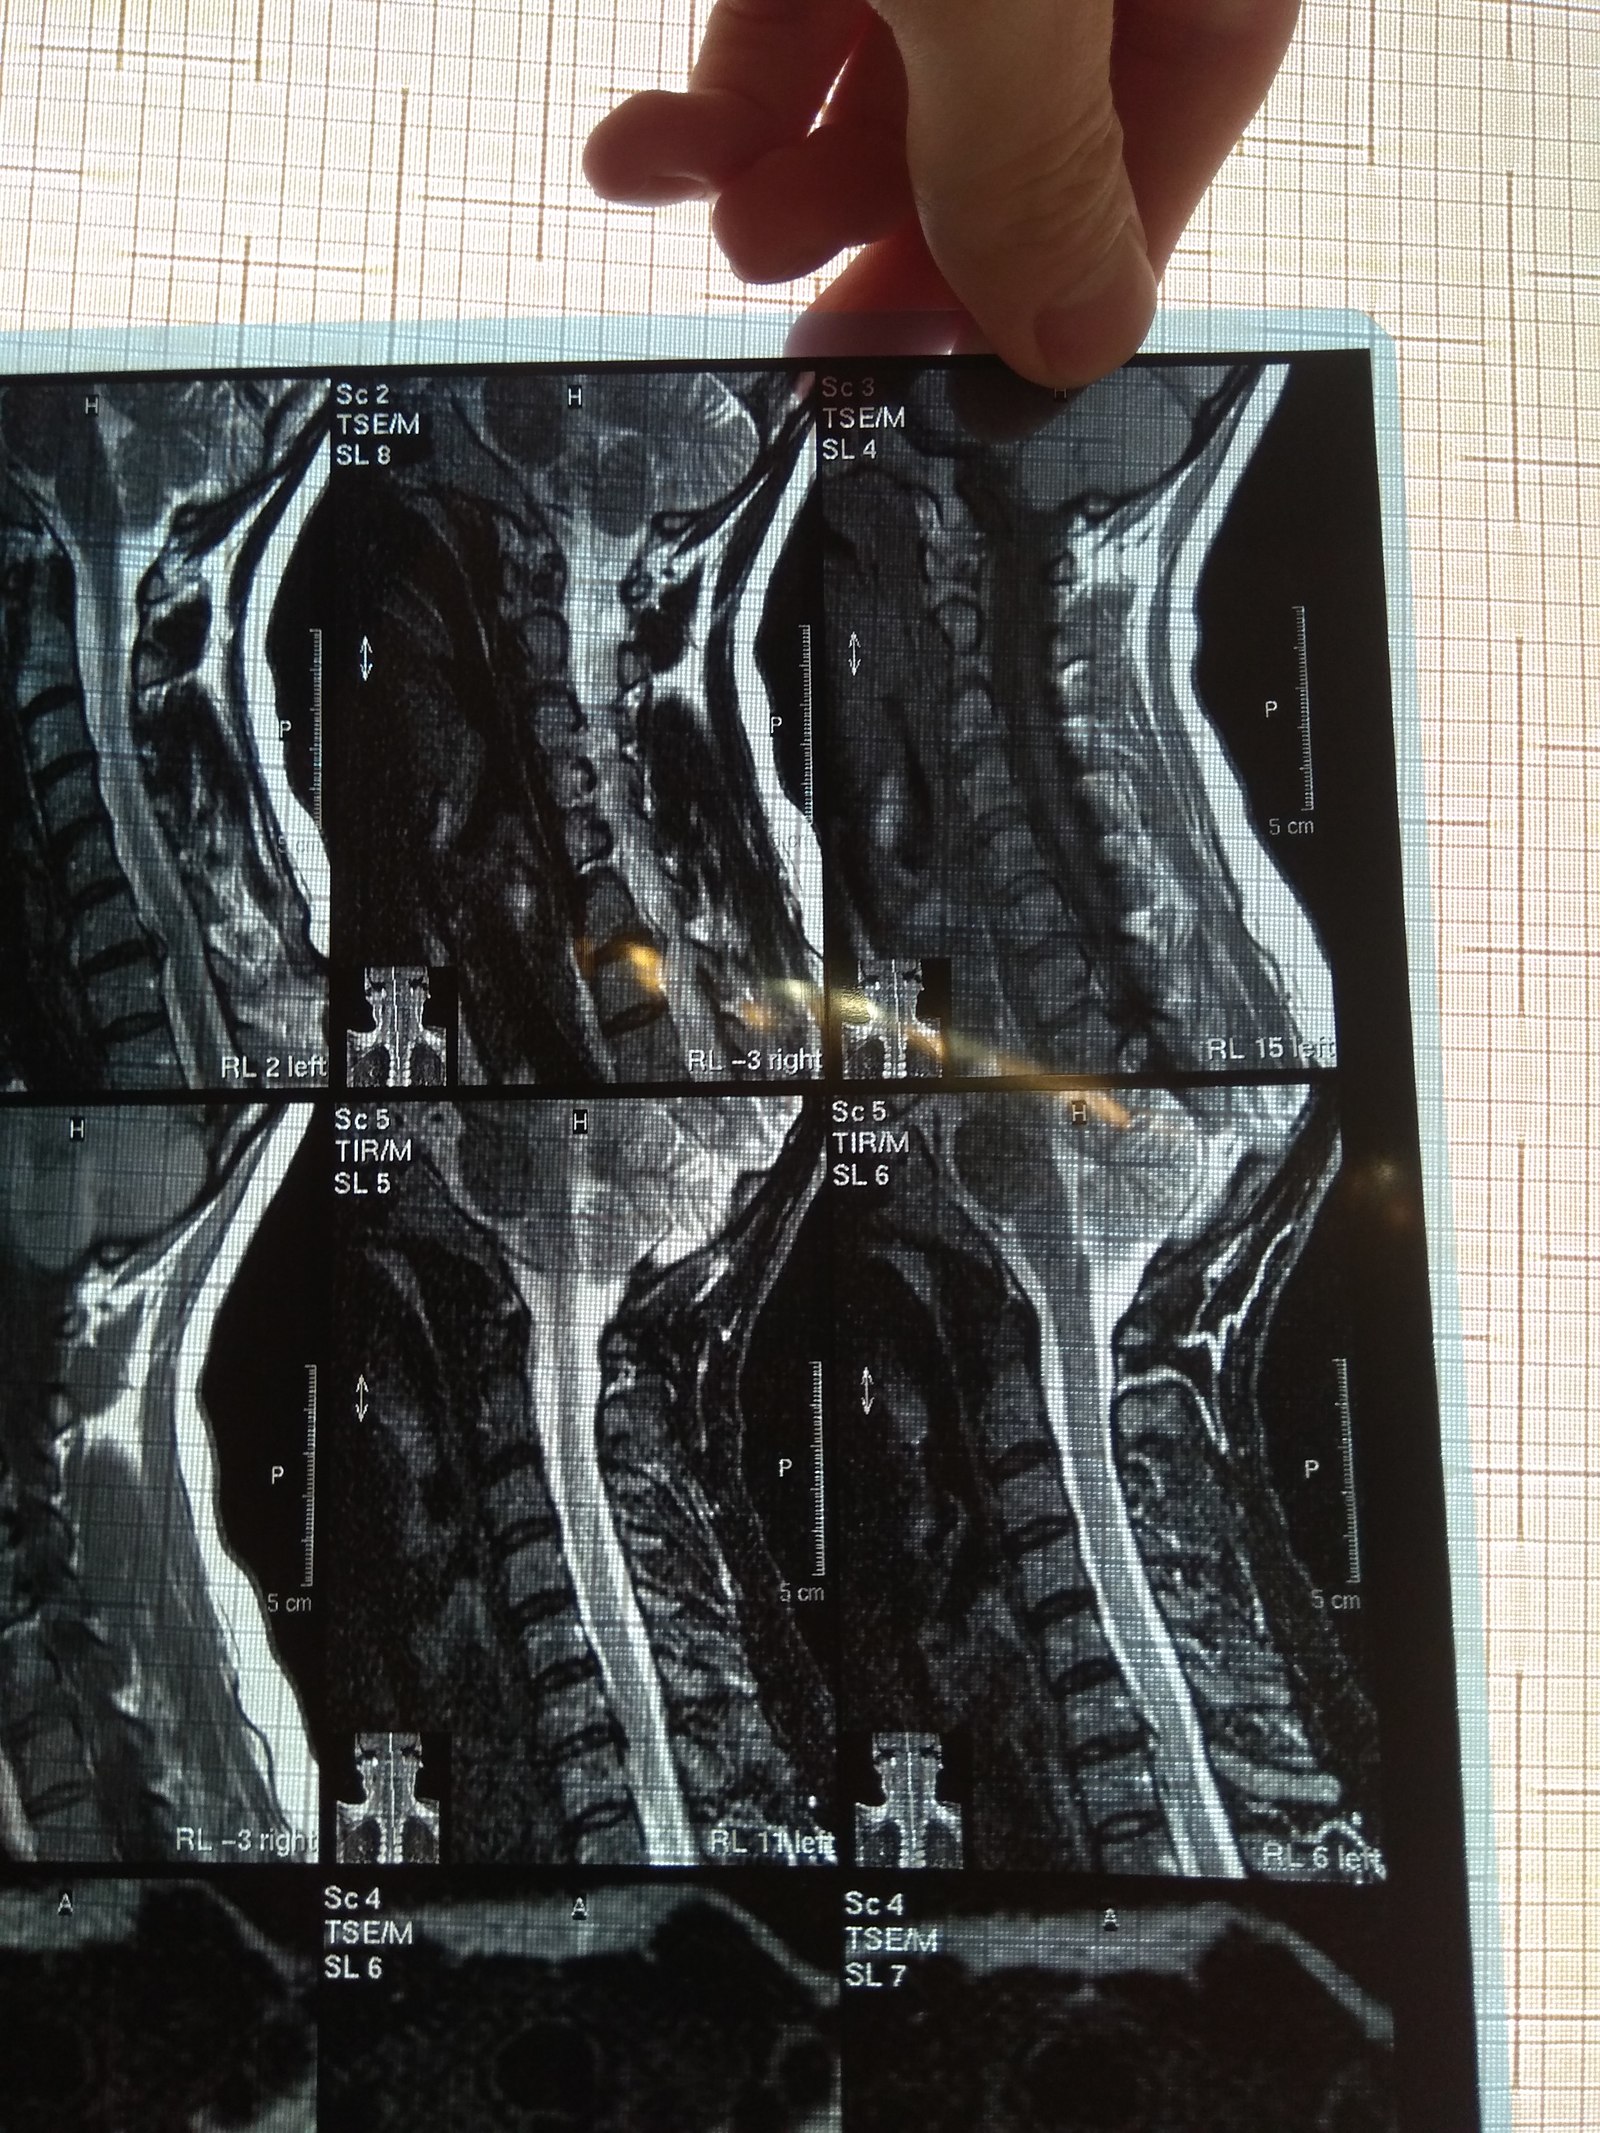

У подруги случилась проблема, тянула с визитом к врачу и в итоге потеряла сознание, вызывали скорую и направили к неврологу. Онемение пальцев на правой руке, сильные боли до судорог и потери сознания. В итоге невролог направил на МРТ и к нейрохирургу, выписали ношение ортопедического воротника, 2 вида уколов и таблетки, названия навскидку не помню. Сказали если через 10 дней не полегчает, то на операцию. Сегодня 5й день, никаких улучшений, рука с каждым днем выше немеет, но подвижность пока в норме. В день по 2-3 раза колет кетонал. Я вот переживаю как бы рука не отказала. Такое может случиться?